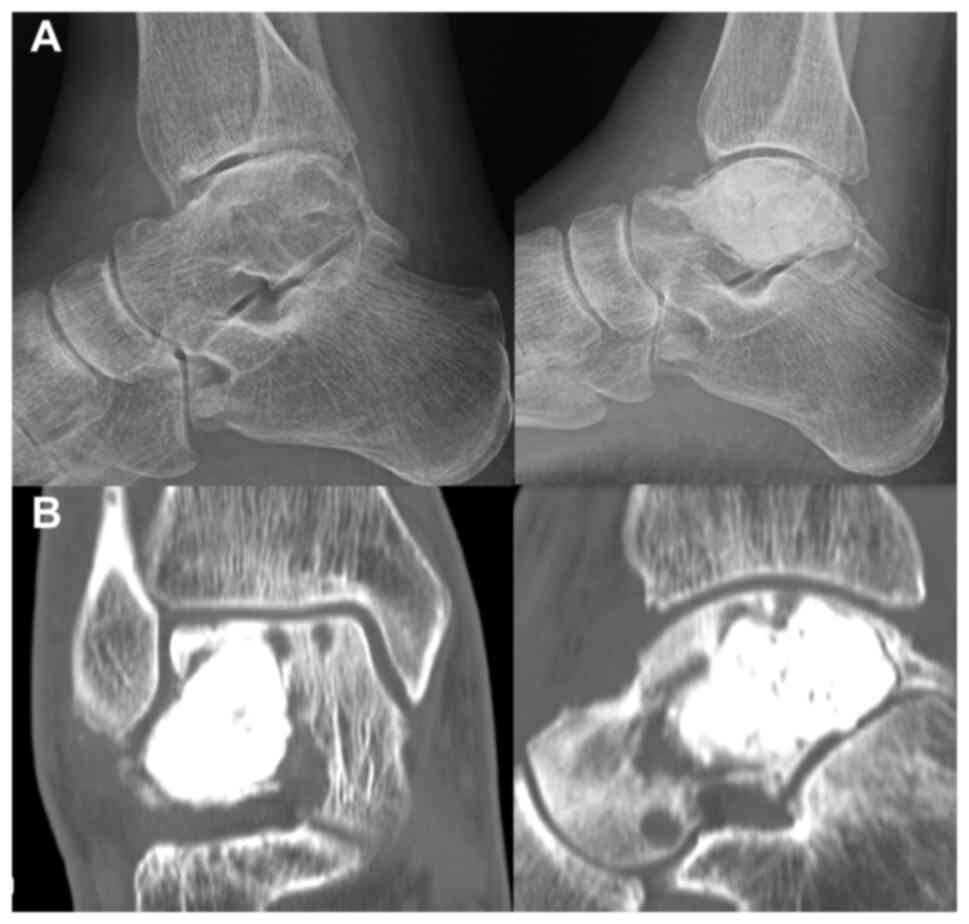

In June 2007, a 50-year-old male presented to the Masaryk Memorial Cancer Institute Sarcoma Center, with a 1-month history of persistent pain in the right ankle. Further investigations showed a cystic lesion of the talus on a CR scan, which was later confirmed by a supplementary CT scan (Fig. 16). The histopathology report diagnosed GCTB with a secondary aneurysmal cyst of the talus (Fig. 17), leading to a recommendation for intralesional resection with bone cement augmentation. After receiving the recommended treatment, the patient returned 5 months later with swelling and increased pain in the ankle. A follow-up CT scan showed destruction of the bone surrounding the bone cement, as well as osteolysis of the calcaneus and the presence of an extraosseous mass proximally (Figs. 16 and 18). Due to the extent of osteolysis, the patient required an astragalectomy. Subsequent histopathology reports showed a diagnosis of giant-cell rich osteosarcoma, contradicting the initial findings (Fig. 19). Further staging scans indicated the presence of lung metastases (Fig. 20). The Musculoskeletal Tumor Committee recommended metastasectomy followed by adjuvant CHT. Despite the successful removal of 12 lung metastases, the patient developed additional lung metastases within two months. Despite palliative care efforts, the patient died 6 months later.

Figure 16.

Case 4. (A) Radiographic images showing a misdiagnosed cystic lesion of the talus (right) alongside the post-cementoplasty results (left). (B) CT scan images showing local recurrence following cementoplasty, initially performed for a misdiagnosed giant-cell rich osteosarcoma